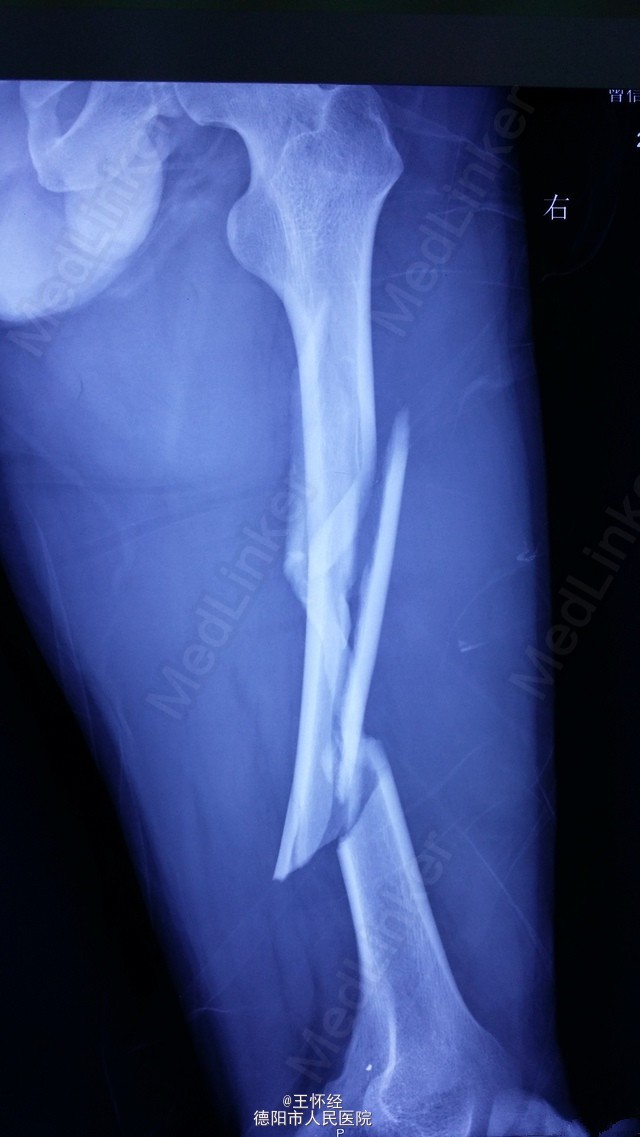

右股骨干粉碎性骨折一例

患者男性,26岁,重物砸伤右大腿后畸形1天,外院转入;予闭合复位髓内钉固定,由于为长节段骨折,骨折距离股骨髁较近,固定不够稳定,术后有骨不连、内固定失效的风险,故加上阻挡钉可以增加骨折固定的稳定性。